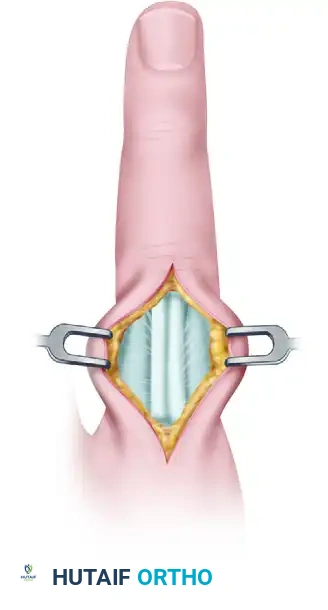

2. Surgical Approach: Volar Bruner Incision:

* Surgeon's Directive: "For FDP avulsions, we utilize a volar Bruner incision. This S-shaped incision provides excellent exposure while protecting the critical neurovascular bundles and minimizing scar contracture. I'm starting distally, just proximal to the DIP joint crease, and extending proximally into the mid-palm if necessary to retrieve a retracted tendon (especially for Type I injuries). Meticulous soft tissue handling is vital to minimize trauma to the skin, and great care must be taken to avoid injury to the germinal matrix proximal to the nail fold."

* Technique: "Incise the skin and subcutaneous tissue. Identify and carefully retract the digital neurovascular bundles, which run along the sides of the flexor sheath. Use fine-tipped forceps and blunt dissection."

3. Exposing the Flexor Tendon Sheath and Pulleys:

* Surgeon's Directive: "Now we expose the flexor tendon sheath. Remember our pulley system: A2, A3, A4, A5. We must preserve the A2 and A4 pulleys, as they are crucial for preventing FDP bowstringing and maintaining efficient finger flexion. I'm carefully incising the C1, A3, and C2 pulleys to gain access to the FDP tendon, but leaving A2 and A4 intact."

* Technique (Dorsal Dislocation, Volar Approach): "Using a small, modified Bruner or lazy-S incision volarly, carefully dissect through the subcutaneous tissue, identifying and protecting the neurovascular bundles. We'll open the flexor tendon sheath. Often, the head of the middle phalanx has 'buttonholed' through the interval between the FDP tendon and the collateral ligaments, with the volar plate potentially interposed. We need to gently retract the FDP tendon and carefully release the interposed volar plate or any other soft tissue blocking reduction."

* Technique (Volar Dislocation, Dorsal Approach): "For a volar dislocation, we'll use a dorsal longitudinal or lazy-S incision. Carefully dissect down to the extensor mechanism. Here, the head of the middle phalanx may have buttonholed through the interval between the terminal extensor tendon and the collateral ligament. We'll gently retract the extensor mechanism and carefully release any interposed structures."